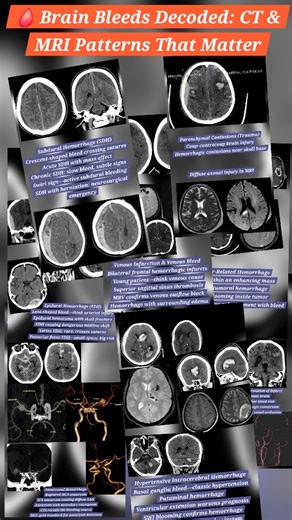

Diagnostic Cerebral Angiography

What is Arteriovenous Malformati…

Carotid Artery Disease & Stroke A…